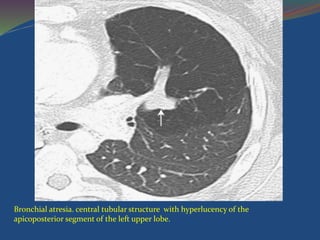

 CT - central, mass like opacity with a tubular

configuration.

 Distal segmental branches are dilated and

contain secretions. The peripheral lung is

hyperexpanded, with decreased attenuation

and reduced vasculature.

Bronchial atresia. central tubular structure with hyperlucency of the

apicoposterior segment of the left upper lobe.